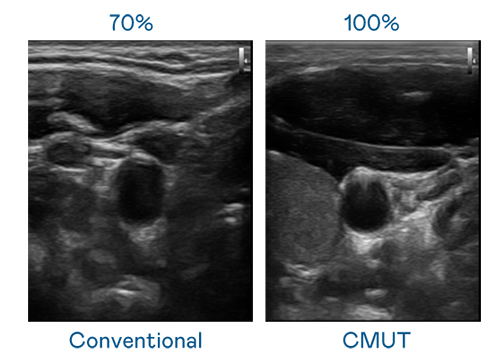

CMUT 技術是一種用電容式微機電元件來產生超音波訊號的技術。與傳統 PZT 壓電式技術相比,CMUT 頻寬增加 30%,更寬頻的超音波訊號讓影像解析度大幅提升,是實現高影像品質醫療超音波掃描、促進精準醫療發展的關鍵技術。

大頻寬帶來超清晰影像

超音波影像的解析度高低,首先取決於探頭能發出的訊號頻寬。火星直播电视tv版免费下载 CMUT 可提供高清晰的超音波訊號,提供高頻寬、高靈敏度、影像紋理細節更高的超音波影像,協助醫護人員縮短影像判讀時間及利用精準的醫療影像進行診斷。